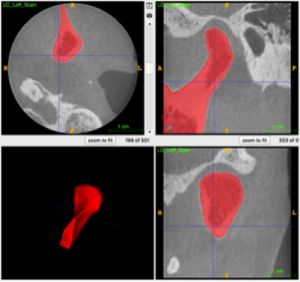

3D-constructive Interference into Steady State (3D-CISS) Labyrinth Signal Alteration in Patients with Vestibular Schwannoma

Publication: Auris Nasus Larynx. 2018 Aug;45(4):702-10. PMID: 28947096 Authors: Wagner F, Herrmann E, Wiest R, Raabe A, Bernasconi C, Caversaccio M, Vibert D. Institutions: Department of Diagnostic and Interventional Neuroradiology, University Hospital, University of Bern, Bern, Switzerland. Abstract: Objective: To evaluate signal intensity of the inner ear using 3D-CISS imaging and correlated signal characteristics in patients with vestibular schwannoma to neuro-otological symptoms. Methods: Sixty patients with unilateral vestibular schwannoma were retrospectively reviewed. All patients had had initial and follow-up magnetic resonance imaging (MRI). Individual treatment strategies consisted of "wait-and-watch", surgical tumour resection, stereotactic radiosurgery or both surgery and stereotactic radiosurgery. For all patients a complete baseline and treatment course neuro-otological examination was re-studied. For the semi-automatic volumetric tumour measurement we used 3D Slicer 4.4.0. Results: On initial MRI, 3D-CISS sequence signal loss of the membranous labyrinth was present in 20 patients (33.3%); signal loss of cochlea in 20 (33.3%) and coincident signal loss of sacculus/utriculus in 17 (85%) of them. Sequential analysis of follow-up MRI series demonstrated slightly increased labyrinthine signal degradation, independently of the chosen therapy. Correlation of initial MRI results with initial neuro-otological symptoms showed significance only for cochlear obstruction versus vertigo (p=0.0397) and sacculus/utriculus obstruction versus vertigo (p=0.0336). No other statistically significant relationships were noted. Conclusion: 3D-constructive interference into steady state (3D-CISS) is appropriate for observing inner ear signal loss in patients with vestibular schwannoma. However, except for vertigo, no significant correlation was noted between initial neuro-otological symptomatology and signal loss of the inner ear. |